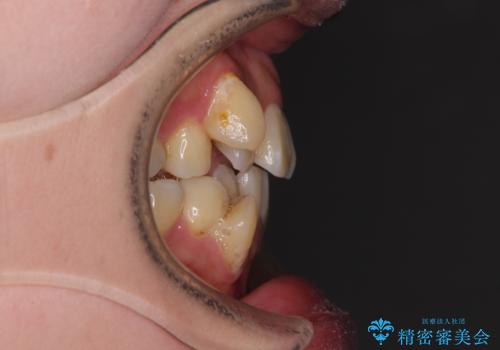

【モニター】上下の八重歯を治したい ワイヤー装置による矯正治療

- 上下前歯のデコボコを気にして来院された患者様です。

デコボコが強いため、非抜歯で矯正をすると出っ歯仕上がりとなるため、上下左右の第一小臼歯4本を抜歯することとしました。